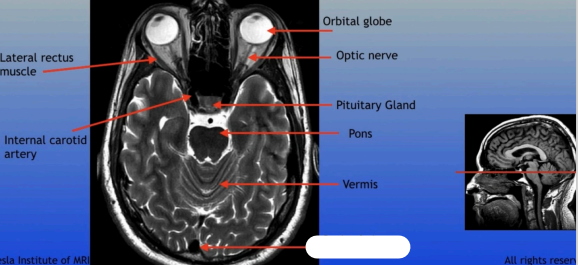

Lateral Rectus Muscle

Internal Carotid Artery

Orbital Globe

Optic Nerve

Pituitary Gland

Pons

Vermis

Sagittal Sinus